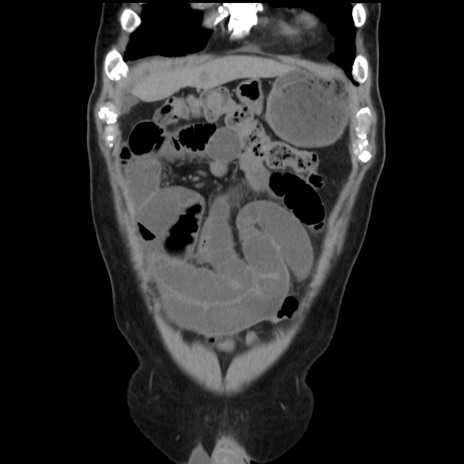

横断像